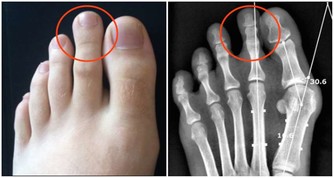

在生活中有兩種現象,一種是有人在痛風發作後,才知道自己的血尿酸水平已經遠超正常值;另一種現像是,在體檢時發現自己尿酸值高,但是,沒有什麼自覺症狀。

眾所周知,一旦尿酸高了,會引發全身性疾病,首當其衝的就是關節疾病,對於腎臟、血管等都會有不同程度的損害,還會影響血糖引發糖尿病等等。

1、困倦口渴

對於高尿酸、痛風患者來說,如果經常無理由的出現口渴,並且大量喝水之後還會感覺到口渴的情況,很有可能就是我們的腎臟毒素積累過多導致的。

因為腎臟需要及時的把這些毒素排出去,但是也需要大量的水分來進行新陳代謝,如果經常出現這樣反常的情況,要注意看一下腎臟是否出現了問題。